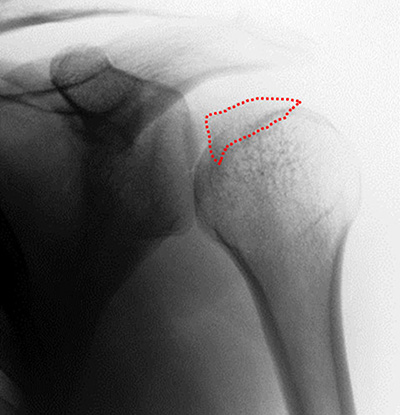

T.A.C.:Luxación posterior con defecto óseo anterior (Fig. 2). Ante dicho hallazgo se realizó reducción incruenta bajo neurolepto analgesia, siendo esta satisfactoria, y se inmovilizó con un cabestrillo. Es controlado en consultorio externo de la especialidad a los 10 días de evolución. Se completaron los estudios.

Figura 2: T.A.C. Simple: Luxación posterior gleno-humeral con defecto óseo en región antero-medial.

Figura 3: Rx. AP Post-Reducción: Imagen de discontinuidad de la interlínea articular, por fragmento óseo.

Figura 4: A) T.A.C. simple: Cuantificación u locación del defecto óseo en la región antero-medial de la superficie articular humeral. Fragmento libre en cavidad. B)3-D: Valoración y cuantificación del fragmento osteo-condral y su relación al momento del estudio.